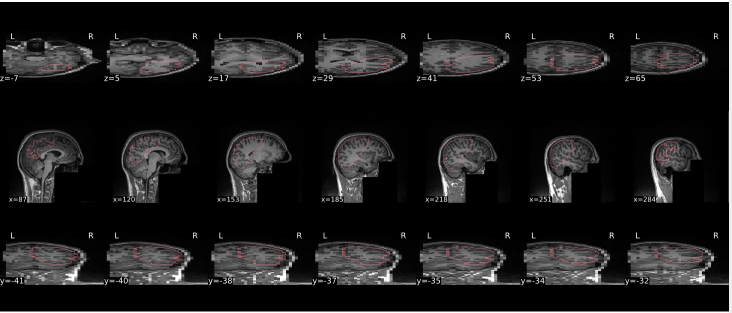

EPI tSNR

In the signal to noise ratio images of the resting state image the desired signal is compared to the amount of background noise. It is important to check all the views (sagittal, coronal, axial) because some artefacts (e.g., stripes) may be evident only in one particular view.

Example of a good subject

- Signal to noise is symmetrically distributed and there is no signal distortion

Example of a bad subject

- Asymmetry

- Potential signal distortion (might represent an artefact)

- Signal drop-out

- Stripes artefact

Clear large artefact (e.g., zebra stripes in example 1) are worth the exclusion of the subject. If you are unsure, check the other quality metrics for that subject to decide whether they should be excluded.

Summary

| good | bad |

|---|---|

| Symmetrical distribution of noise and signal | Asymmetry |

| No disruptions of the signal (no “black patches”) |

Potential signal disruptions (could be related to artefacts) |

| No stripes (sign of high motion) |

Signal drop |

| Stripe artefacts (“zebra” stripes due to motion) |